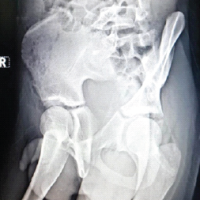

Subsequently, a compression bandage was applied. The patient did not receive any antibiotics or anti-inflammatory drugs and was instructed to come back on the 10th day of suture removal and later if experienced considerable pain or if the cyst returned. Day 10 follow-up showed no signs of infection (Fig. 3a and b). The 6-month follow-up revealed no recurrence, an excellent outcome, and wound healing (Fig. 4a and b).

Figure 3: (a and b) Days of follow-up.

Figure 4: (a and b) 6 month Follow-up.